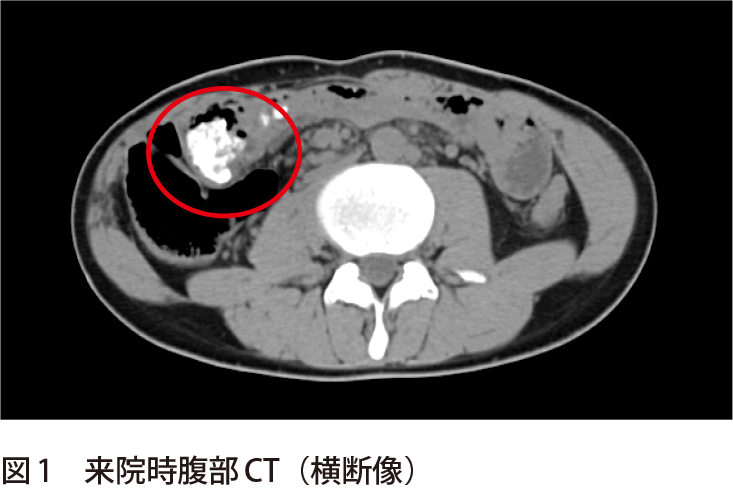

薬物中毒者の悲惨な末路 ロシアから、恐るべき新型麻薬の報告がありました。 スーパーセルとは?超巨大積乱雲を画像と動画で観察する ;薬物中毒の診断に苦慮することがある。そこで,放 射線透過性の低い物質の検出に優れているCT 検査 解せずに沈殿し,高密度のためCT 画像上高吸収域 を示したと考えている。 本検討では腹部CT による急性薬物中毒の診断能 Fig 1 A case of overdose with a high density area薬物中毒女性 ストック動画ロイヤリティフリー映像素材 若い女性は薬をたくさん飲みます。 うつ病の薬物中毒の女性がヘロイン注射器を手に床に横たわっている。 女性中毒者が注射器でヘロインを注射してる。 中毒とJunkie 十代の少女。 薬物中毒

急性中毒(特に薬物中毒) 阿南 英明 〔日内会誌 102:455~460,13〕 Keywords 意識障害,トキシドローム,胃洗浄,簡易薬物検査,日本中毒情報センター はじめに 急性中毒とは,人体にとって有毒な物質が体 内に入って急性に様々な症状を呈することをい う.急性中毒患者が受診する場面とし慢性中毒:薬物依存症の方がさらに乱用を繰り返した結果、慢性的に生じる症状です。幻覚や妄想のほか、無動機症候群(無気力、集中力・注意力の低下、疲れやすいなど)の症状がみられます。 薬物依存の治療 薬物依存症は慢性疾患と同じ 「精神的依存」の項で説明した通り、薬物依存症画像は麻薬中毒者用リハビリ施設のマッチングサイトRehabscomからの引用です。 Before and After Drugs (Meth) via Rehabscom わずか数年でビックリするほど容姿が変わっていますね。 画像に挙げてあるメス常習者の外見的特徴は以下(意訳)。

解答 解説 大量の発汗 頻脈 意識障害で搬送された若年男性 実践 画像診断q A 羊土社 レジデントノート 羊土社